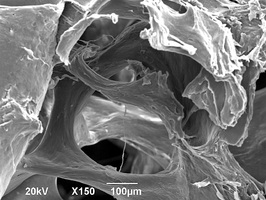

Биоимплантаты аллогенные стерильные губчатые механически и и ультразвуком обработанные.

По внешнему виду представляет собой пористый губчатый блок номинального размера.

2. Поверхность и структура материала для изготовления биоимплантатов